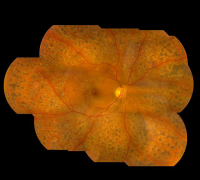

糖尿病患者視網(wǎng)膜病變?cè)谔悄虿』颊咧惺值膹V泛,患病率十分的高,而且會(huì)伴隨著現(xiàn)病史的增加而迅速提升。糖齡超出三年的,發(fā)病率大概在5%;糖齡超出5年的已達(dá)25%;超出十年糖齡...